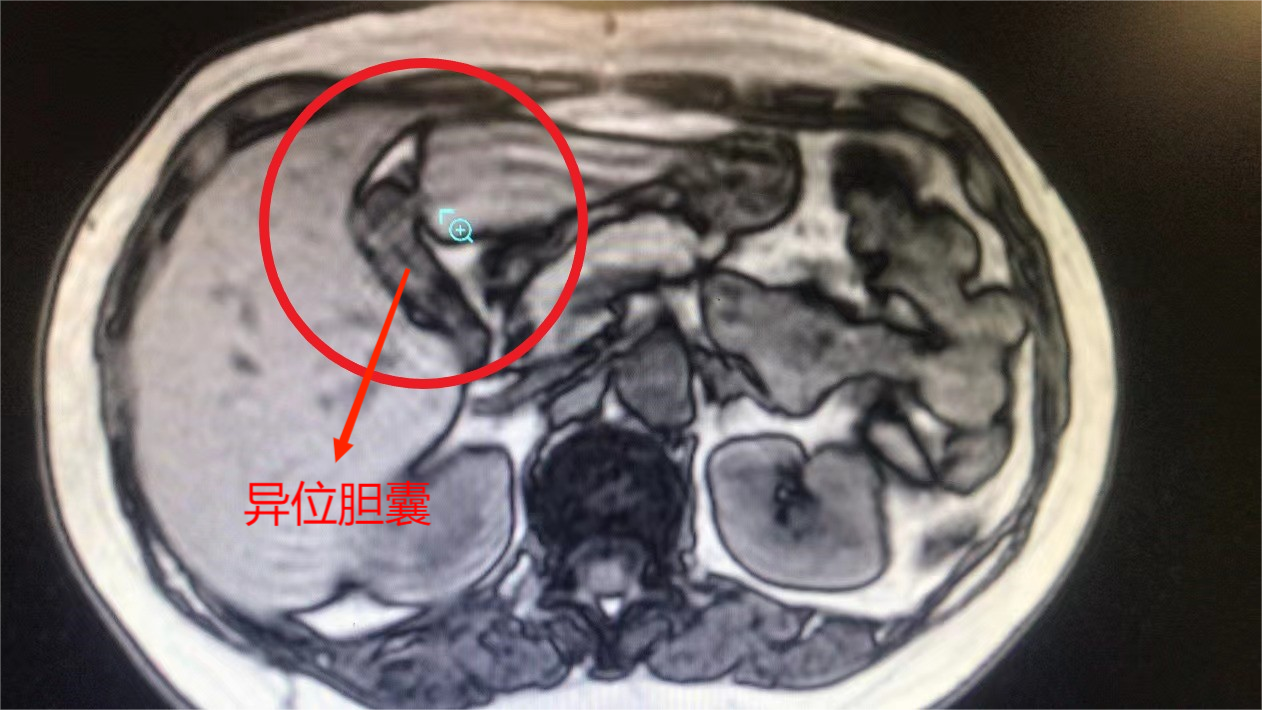

胆囊错位生长

刘女士今年55岁,因“反复右上腹痛1年,再发并加剧1天。”在2022年6月5日 来到恒生医院就诊,入院后完善相关检查,磁共振提示异位胆囊,胆囊多发结石并胆囊炎。术前检查无明显手术禁忌症,于2022年6月7日在全麻下行腹腔镜胆囊切除术,因患者肝左叶异位胆囊导致胆囊动脉、肝动脉变异,手术难度很大。

程明主任介绍到,异位胆囊在体检中偶有发现,但在临床中比较少见,尤其是肝左叶异位胆囊更少见,而肝左叶异位胆囊且不是镜像人(内脏全反位)的患者更是少之又少,近几年仅有零星文献报导。